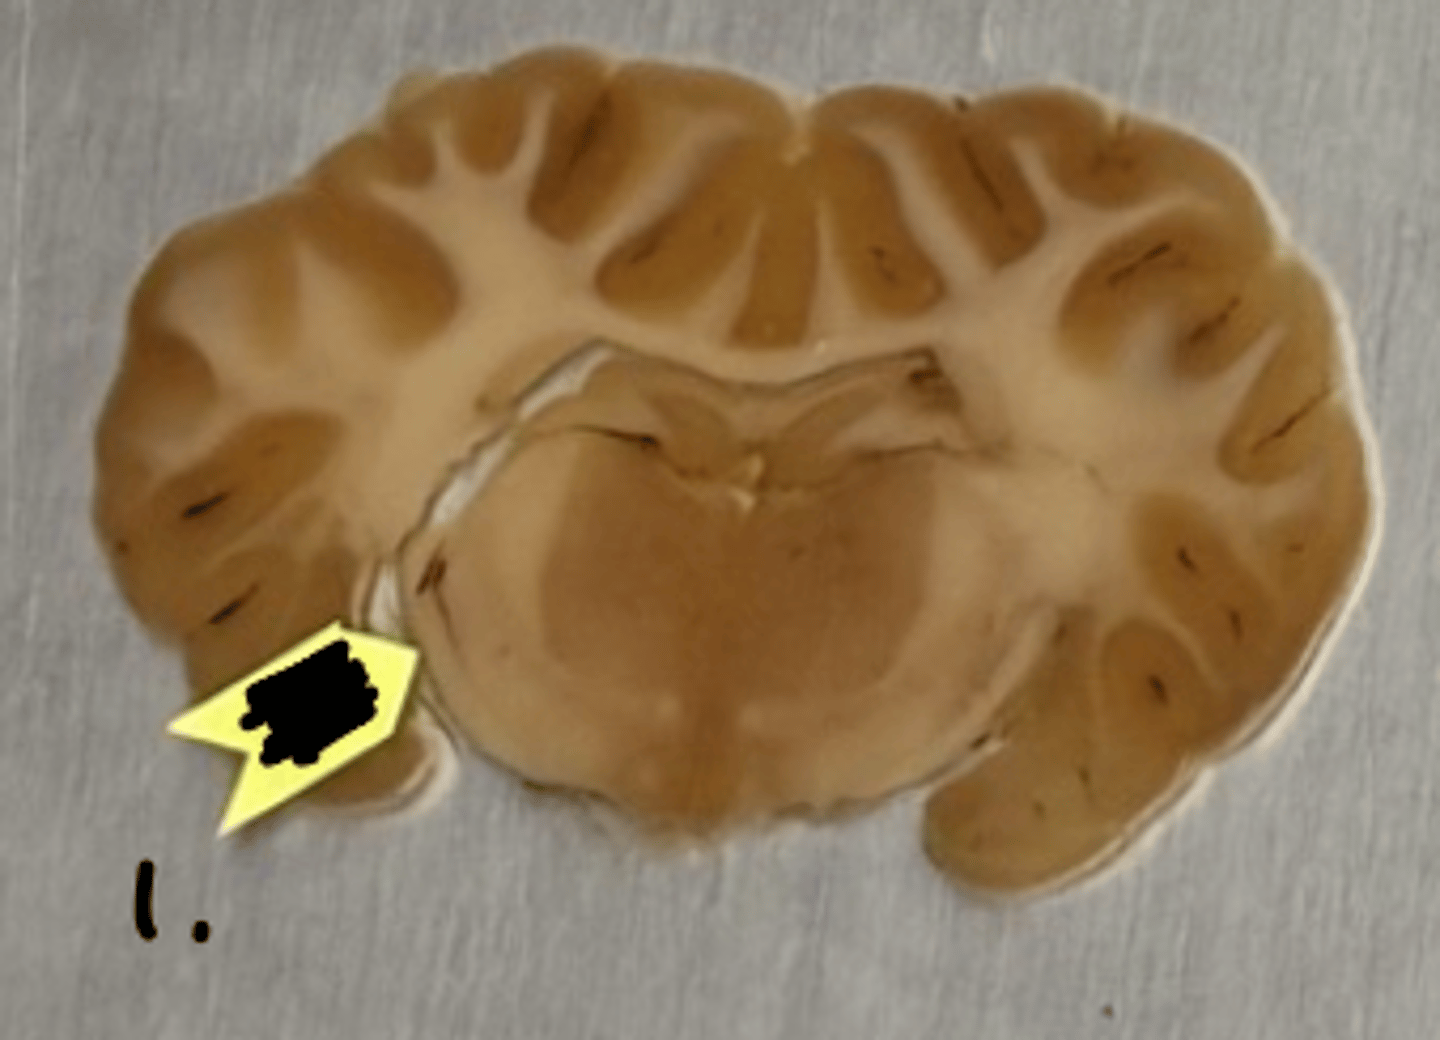

optic chiasm

what structure is labeled as #1 ?

optic tract

what structure is labeled as #2 ?